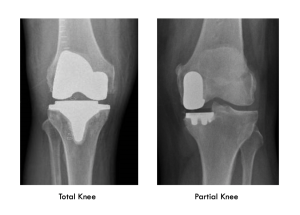

What is the difference between partial and total knee replacement?

Knee replacements are evolving all the time. The term knee replacement is actually fairly historic now as we mostly are only making very fine cuts to put new surfaces on the joint rather than replacing the knee bones.

The knee has three ‘compartments’: and outside and inside knuckle and an anterior compartment made by the knee cap joint. Total Knee Replacement resurfaces all three of these compartments in one go.

A ‘partial’ knee replacement is where the arthritis is mostly only affecting one of the three compartments and so only one compartment is resurfaced.

This can be done in up to 50% of cases and has the advantage of keeping most of your own knee with a quicker recovery from the surgery and a more normal feeling knee afterwards.